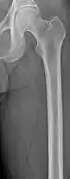

Medical imaging

The diagnostic examination of a person with suspected multiple myeloma typically includes a skeletal survey. This is a series of X-rays of the skull, axial skeleton, and proximal long bones. Myeloma activity sometimes appears as "lytic lesions" (with local disappearance of normal bone due to resorption). And on the skull X-ray as "punched-out lesions" (pepper-pot skull). Lesions may also be sclerotic, which is seen as radiodense.[47] Overall, the radiodensity of myeloma is between −30 and 120 Hounsfield units (HU).[48] Magnetic resonance imaging is more sensitive than simple X-rays in the detection of lytic lesions, and may supersede a skeletal survey, especially when vertebral disease is suspected. Occasionally, a CT scan is performed to measure the size of soft-tissue plasmacytomas. Bone scans are typically not of any additional value in the workup of people with myeloma (no new bone formation; lytic lesions not well visualized on bone scan).